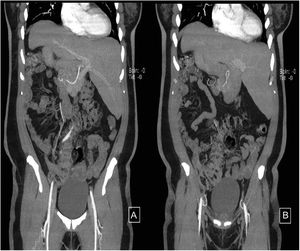

A 44-year-old woman began her illness with colicky epigastric pain that radiated to the right scapula, accompanied by nausea and vomiting. Her leukocyte count was 17,000 and bilirubin values were normal. She sought medical attention at the emergency room of a nonlocal hospital. A laparoscopic cholecystectomy was performed but there were intraoperative difficulties for identifying anatomic structures. The procedure was interrupted and a cholecystostomy tube was placed. She was referred to the Hospital General de México, where new radiologic studies and endoscopic retrograde cholangiopancreatography (ERCP) were carried out. A catheter was identified in the gallbladder, the intrahepatic bile duct was not dilated, and the common bile duct was regular, with a 4 mm diameter. Ultrasound imaging (Fig. 1A–D) and cholangiography through the cholecystostomy tube (Fig. 2A–D) showed a cystic gallbladder with stones, an unaltered intrahepatic bile duct located on the left, no evidence of biliary filling defects, and adequate passage of the contrast medium into the duodenum. The diagnosis of situs inversus was suspected and cholangioresonance imaging (Fig. 3A and B) was carried out, confirming the diagnosis. The study reported gallstones, the presence of a catheter in the gallbladder, and abdominal situs inversus totalis. Laparoscopic cholecystectomy was performed with no complications.